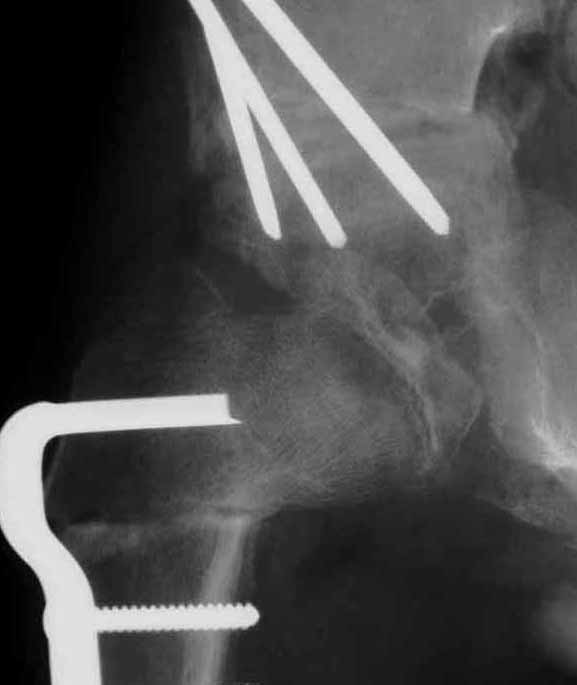

1)大腿骨近位内反切り術。大腿骨の股関節に近いところで人工的な骨折を作り大腿骨頭の向きを変え臼蓋の奥深くに入れることを目的としています。包み込む効果は大きく、さらに大腿骨頭への圧力が減少するので骨形成が早くなります。問題点は、向きを大きく変えた場合下肢短縮がおこることです。ただし、多くの場合数年以内には手術した側の大腿骨は過成長してやがて脚長差は目立たなります。

左図は手術前です。骨頭の外側の1部が臼蓋からはみだしています。右図のように骨切りをおこなって、骨頭の向きを変え、はみだした部分までも完全に臼蓋の奥深くに包み込みます。この手術は術前に骨の正確な計測を行い、手術ではその計画を厳密に実行します。皮膚切開の後には、筋肉の剥離、骨の展開、関節包の温存、金属の打ち込む方向、注意深い骨切り、下肢短縮を最小限に押さえる工夫、など、いずれをとっても慣れた術者が行わないと(少なくとも50例の経験は必要)重篤な合併症をおこすことがあります。

ペルテス病にたいするこの手術の所要時間は平均1時間48分です。

最近では固定材料が改良され、強固な固定が可能となりました。したがって、新しいプレートを使って大腿骨単独手術の場合(骨盤手術を合併しない場合)はギブス期間が3週前後に短縮されます。ギブス除去後には座位ならびに松葉づえ歩行が開始されます。